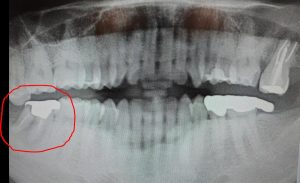

糖尿病だけでなく、生活習慣病を治療するにあたって、大きな問題の一つが治療中断です。けがや他の病気と違って、痛くもかゆくもないのに、病院に行って薬をもらってお金を払う、というのは確かに大変だと思います。私は、よく歯医者さんと似たようなもんと話しています。痛くない時に治療しておけば、歯も守られるし医療費も安い、でも本当に痛くなってからでは、費用も時間もかかって、歯は抜かれてしまいますから。今年の冬は、結局仕事を休んで行く羽目になりました。悪い例ですが、なかなか休みづらいんですよね。下のマニュアルにも書かれています。